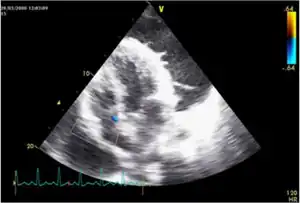

Tuberculous pericarditis is a form of pericarditis.